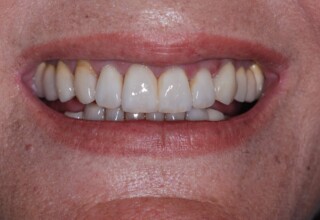

Initial smile

Final Smile